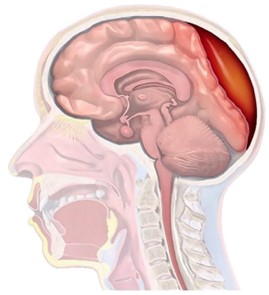

Hematoma Subdural: Lo que Necesitas Saber

El hematoma subdural es una acumulación de sangre en el espacio subdural, es decir, entre la super...